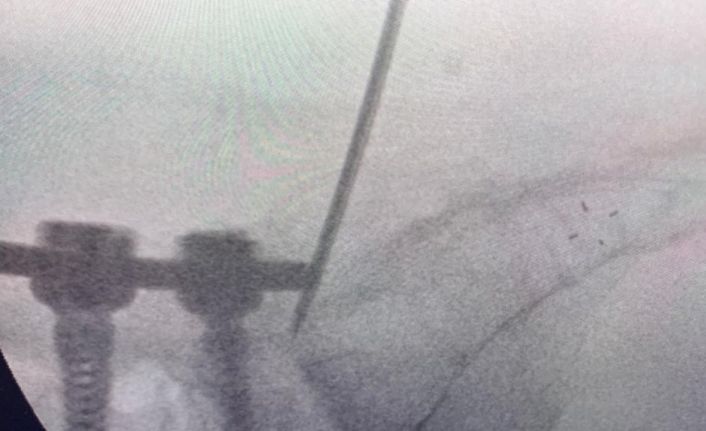

Uzun süre, vidayı çıkarmadan kemik çimentosunu koyma konusunda çalışmalar yaptığını belirten Prof. Dr. Yücesoy, “Kapalı bel fıtığı ameliyatlarında iğneyle sinirin altına girerek izlediğimiz bir yol var. ‘Hastaların kemiğinin içine bu yoldan girilebilir’ diye düşündüm ve bunu da uygulamaya başladım. Bu yöntemde, hastaya lokal anestezi uyguluyoruz. Kıkırdağın olduğu bölümden diskin içine iğneyle girip oradan da kemiğin içine ulaşıyoruz ve çimentoyu koyuyoruz. Bu daha önce hiç uygulanmamış bir yol. Kırılmış vidalı bir kemiğe ilk kez o vidayı çıkarmadan kapalı yöntemle girip müdahale etmiş olduk” diye konuştu.